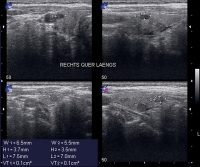

Abbildung 1: Sonographiebefund: Quer- und Längsschnitt: echoarmer Knoten mit Halo im linken Schilddrüsenlappen